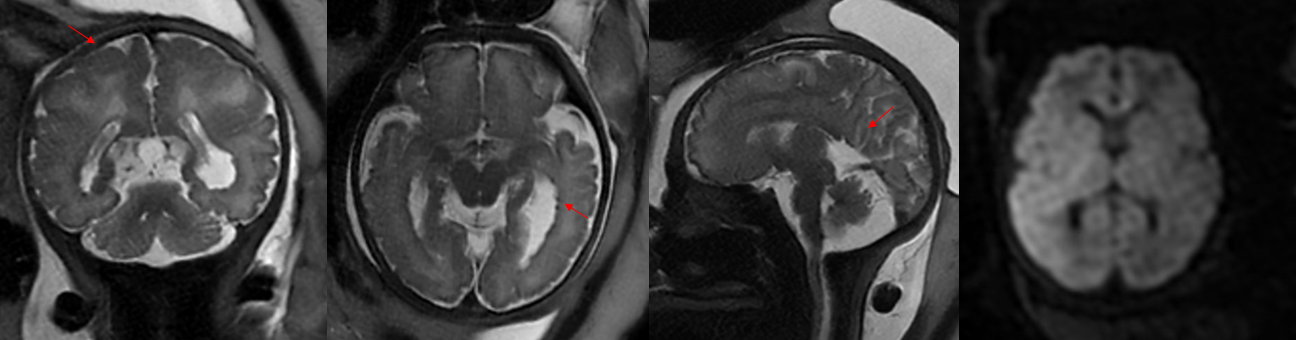

每33秒出生一个缺陷儿

根据2012年卫生部《中国出生缺陷防治报告(2012)》白皮书指出,我国是出生缺陷高发国家之一,新生儿出生缺陷发生率约为5.6%,每年新增出生缺陷患儿约90万例,目前已知的人类出生缺陷疾病达8000—10000种。预防出生缺陷是全球重大医学课题,亦是民生健康刚需。

出生缺陷,会给家庭带来沉重的精神和经济负担,严重影响家庭的幸福和生活质量。